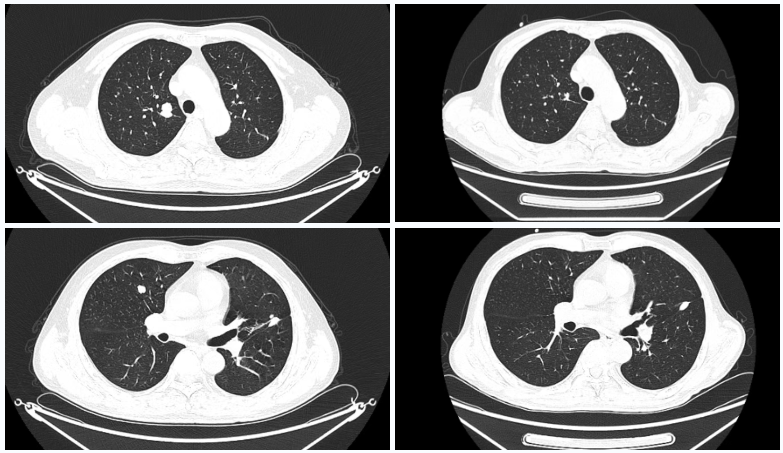

△2023年2月患者基线时CT(左)与2024年4月时CT(右)检查所见对比

△2025年8月疗效评估时患者CT检查(右)较基线(左)对比